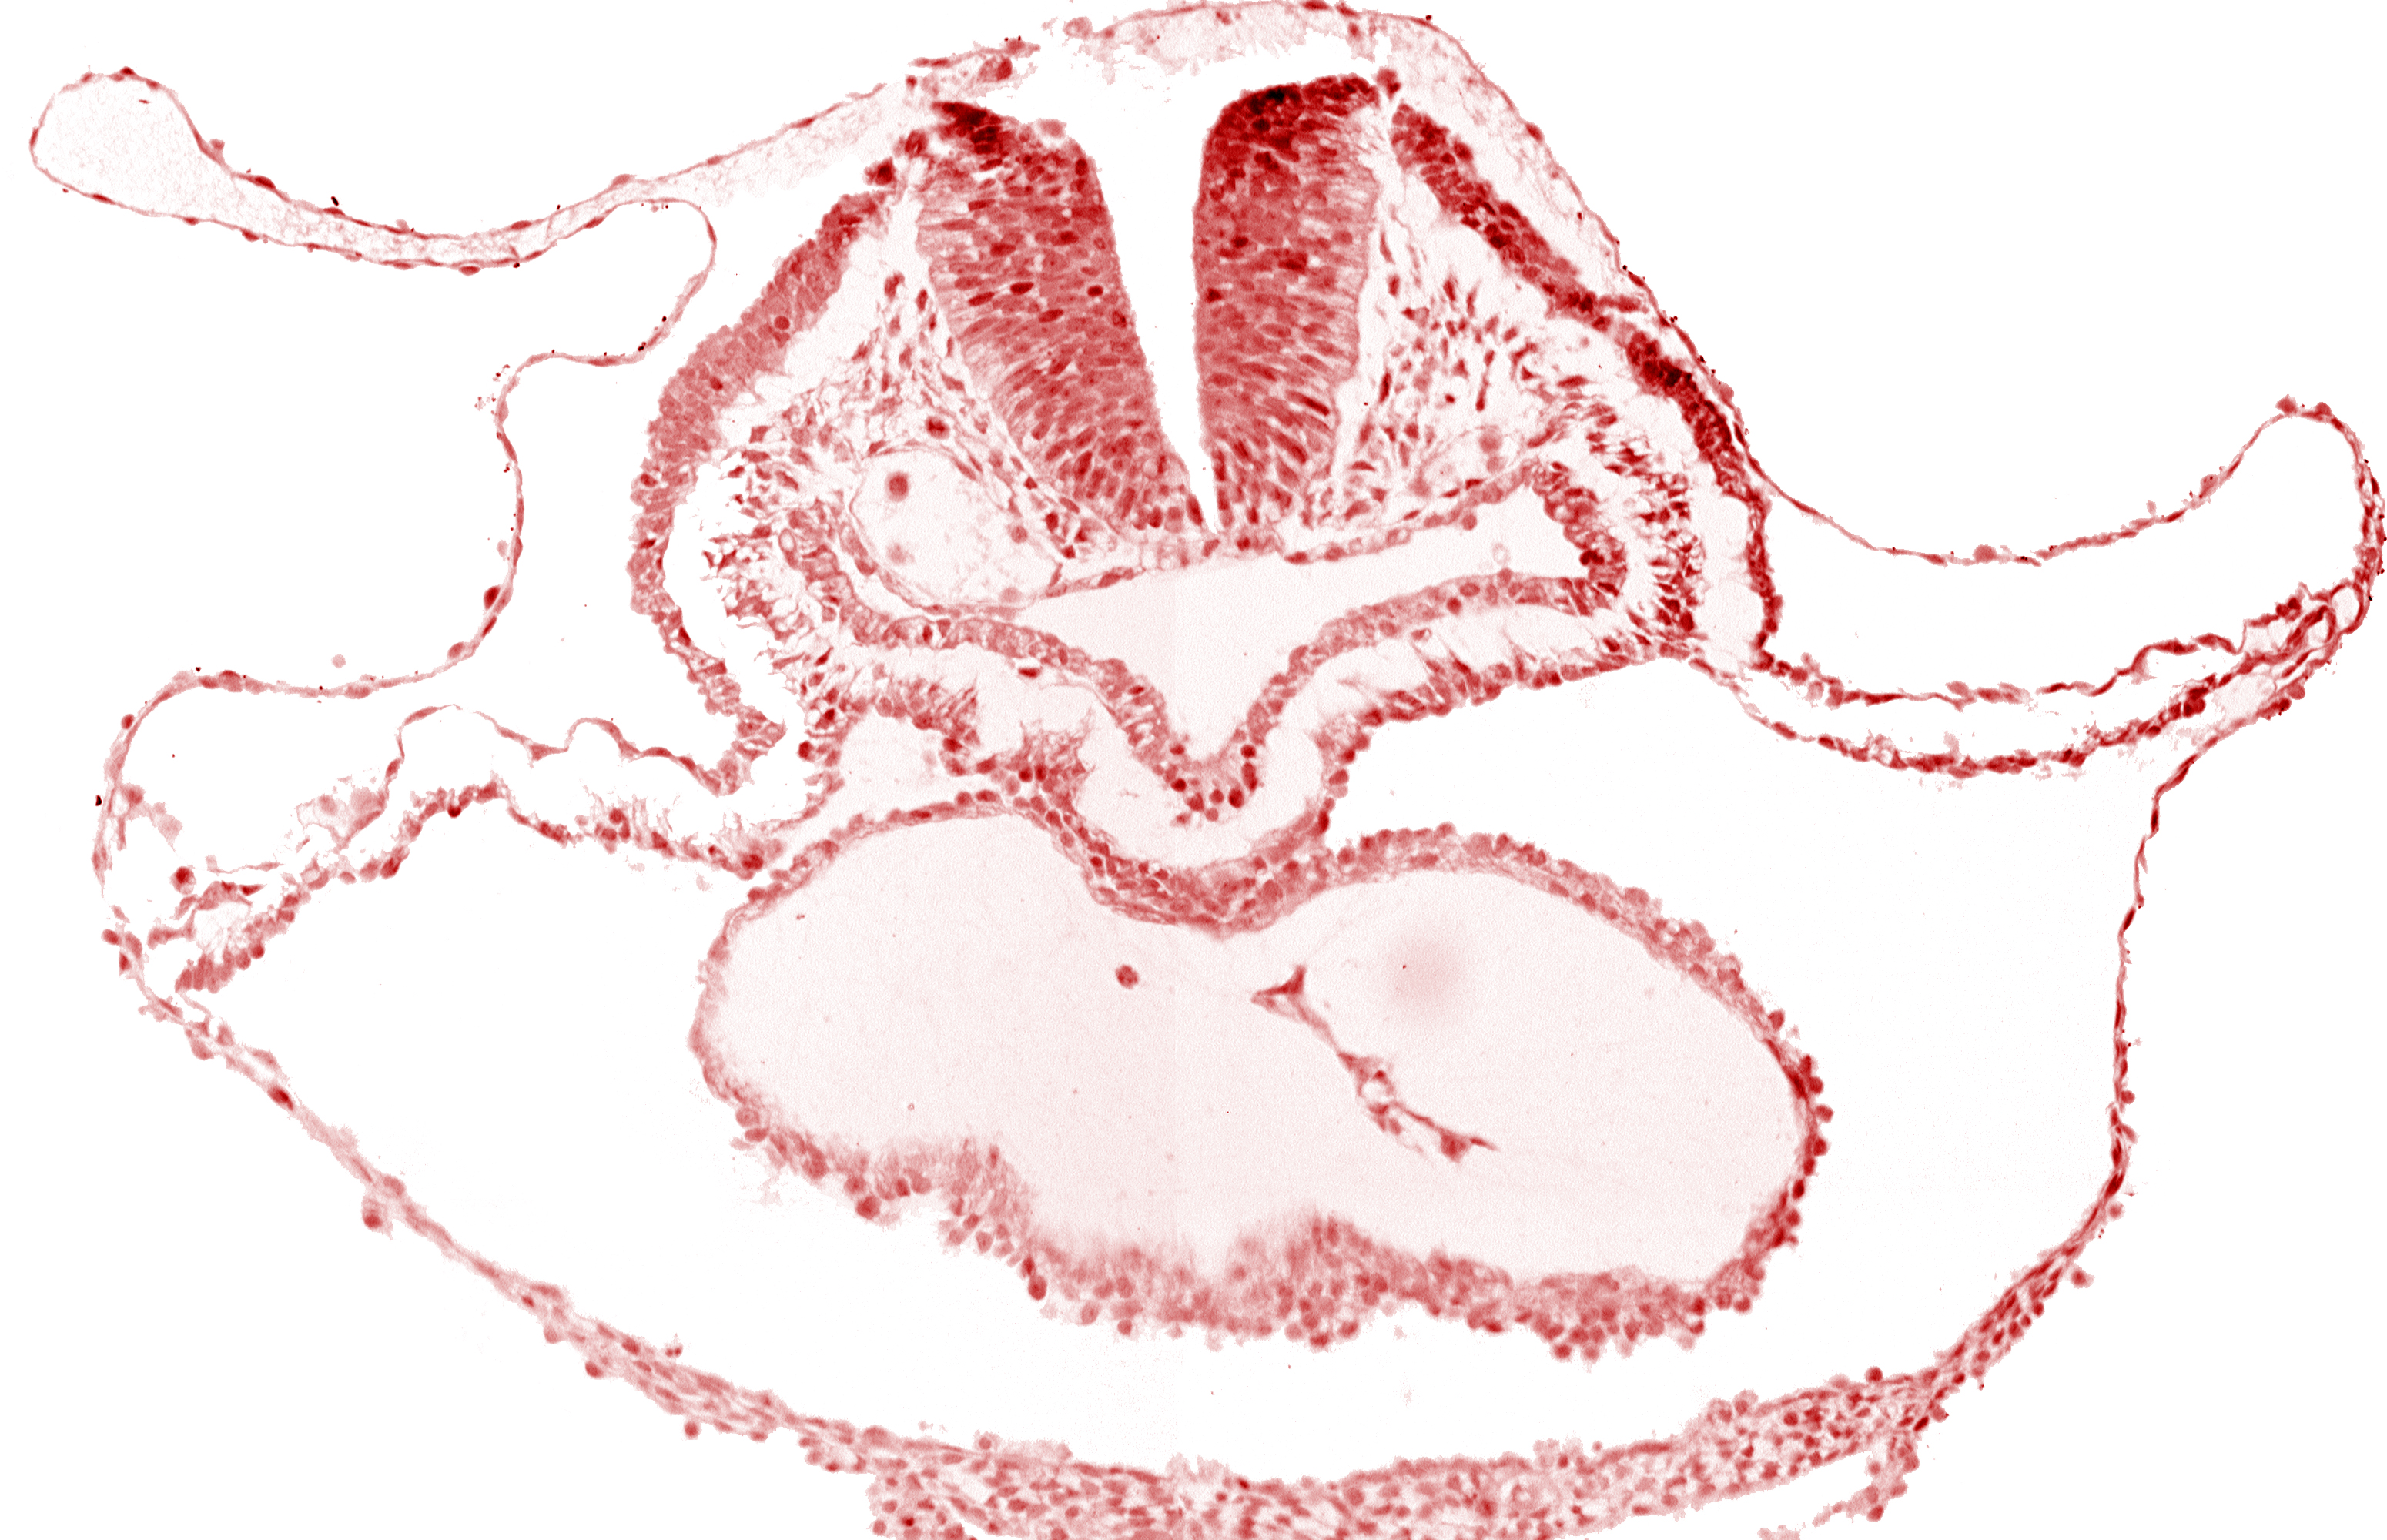

cephalic neuropore, dorsal aorta, lateral pharyngeal recess, median pharyngeal groove, neural fold [rhombencephalon (Rh. B)], pericardial cavity, presumptive left ventricle, right bulboventricular sulcus

Keywords: cephalic neuropore, dorsal aorta, lateral pharyngeal recess, median pharyngeal groove, neural fold [rhombencephalon (Rh. B)], pericardial cavity, presumptive left ventricle, right bulboventricular sulcus